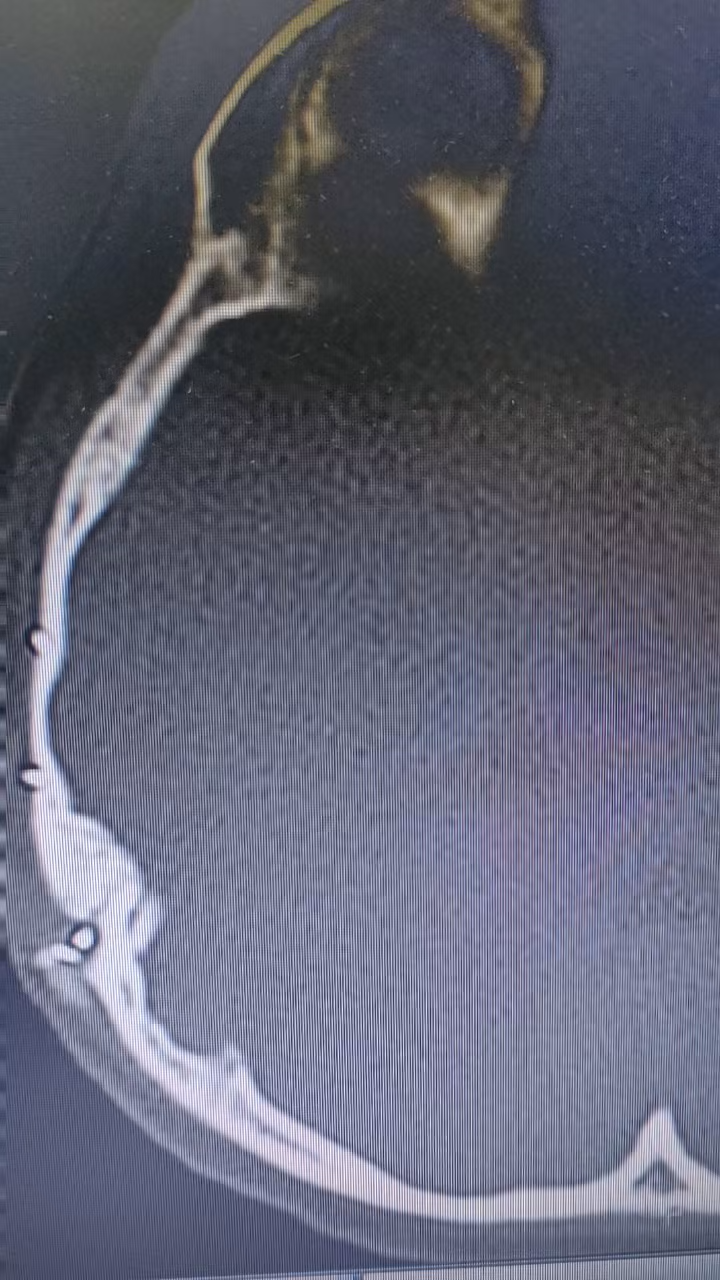

我院CT如下:

为检查鼻窦炎,2023-05-10CT